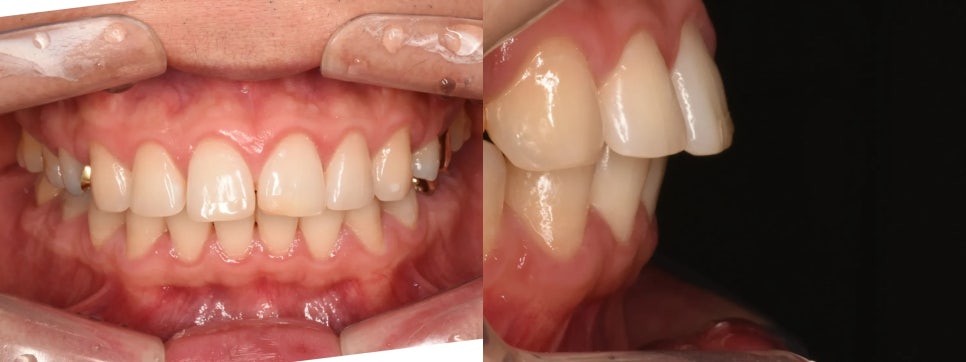

구강 내 사진을 확인해 보니 치아 사이에 약간의 공간(spacing)이 존재했습니다. 아마도 이전 교정 이후 약간의 재발이 있었던 것 같습니다. 또한 교합 사진에서는 윗앞니가 아랫앞니를 약간은 과도하게 덮는 과개교합(딥바이트)이 확인되었습니다.

심각한 문제가 있었다고는 할 수 없으나, 이미 발치 교정 이력이 있음에도 불구하고 특히 얼굴사진에서는 돌출감이 남아있었고, 전반적인 치아 배열 역시 완벽하지 않은 상태였습니다. 무엇보다도, 환자분이 스스로 "입을 넣고 싶다" 생각하셨다는 점이 중요했습니다. 무엇보다도 중요한 것이 자기 만족이니까요.

경등도의 돌출입이 확인됩니다

교정 완료 후 구강 내 사진을 보면, 치열이 깔끔하게 정리되었고 돌출감도 상당히 개선된 것을 확인할 수 있습니다. 한 가지 참고사항으로, 왼쪽 위 앞니 앞쪽 면이 약간 마모되어 있어 추후 레진 치료로 보완하실 예정입니다.

교정 완료 후 – 치열이 정리되고 돌출이 개선되었습니다